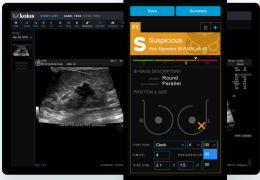

工作流智能。

在这里,先进的智能功能自动执行手动任务和工作流程步骤,以简化流程,提高技术人员工作效率,节省时间和金钱,并增强患者护理。

自动化设备定位和患者姿势确认可优化放射科技师的效率并加快工作流程。

自动技术选择可改善影像一致性并支持辐射剂量控制。

通过任务自动化功能改进感染控制,使放射科技师不再与潜在感染患者直接接触。